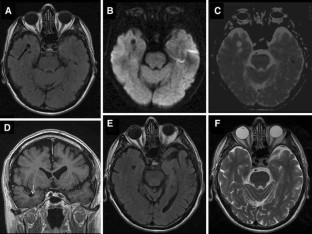

Fig. 1

Patient 1 was a 76-year-old woman with right hemiparesis and aphasia from a left cranial vault meningioma infiltrating the superior sagittal sinus, and a left temporal lobe giant perivascular space. Patient 2 was a 70-year-old man with pituitary apoplexy, vasospasm, cerebral ischemia, and two dPVSs, one in the right temporal lobe, and one in the left anterior perforate substance. Patient 3 was a 78-year-old man with a generalized seizure, and a right temporal lobe dPVS.

In all the patients, temporal lobe giant or dPVSs underwent regression, following meningioma subtotal resection (patient 1) or pituitary lesion shrinkage (patient 2), or spontaneously (patient 3). In patient 2, the left anterior perforate substance dPVS was unchanged.